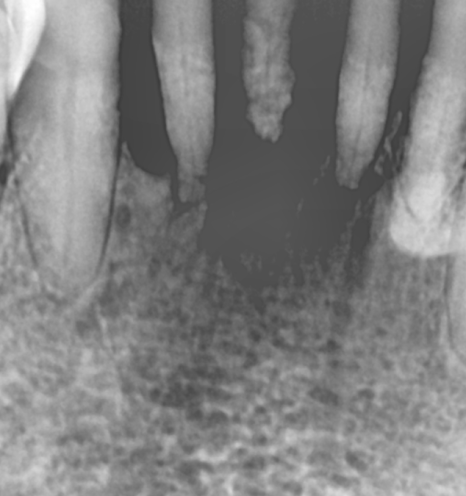

그래서 치아 뿌리 상태를 확인하는

작은 x-ray도 찍고

평가하였습니다.